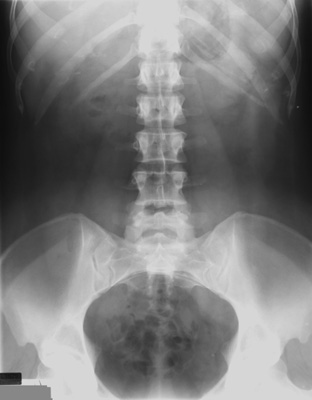

- Evaluate preliminary plain radiograph of the

abdomen for

- relative contraindications (retained stool or

contrast material in colon)

- absolute contraindications to performing

a barium enema (i.e., free air, rigid abdomen).